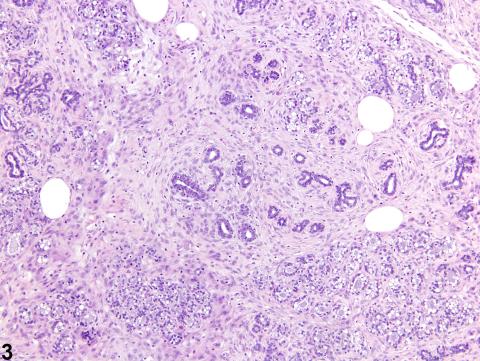

Mammary gland - Fibrosis in a female F344/N rat from a chronic study. Diffuse sheets of mature fibrous connective tissue are a feature of concurrent lobular hyperplasia in the mammary gland.

Mammary gland - Fibrosis in a female F344/N rat from a chronic study (higher magnification of Figure 3). A diffuse sheet of mature fibrous connective tissue surrounds mammary gland ducts and alveoli.